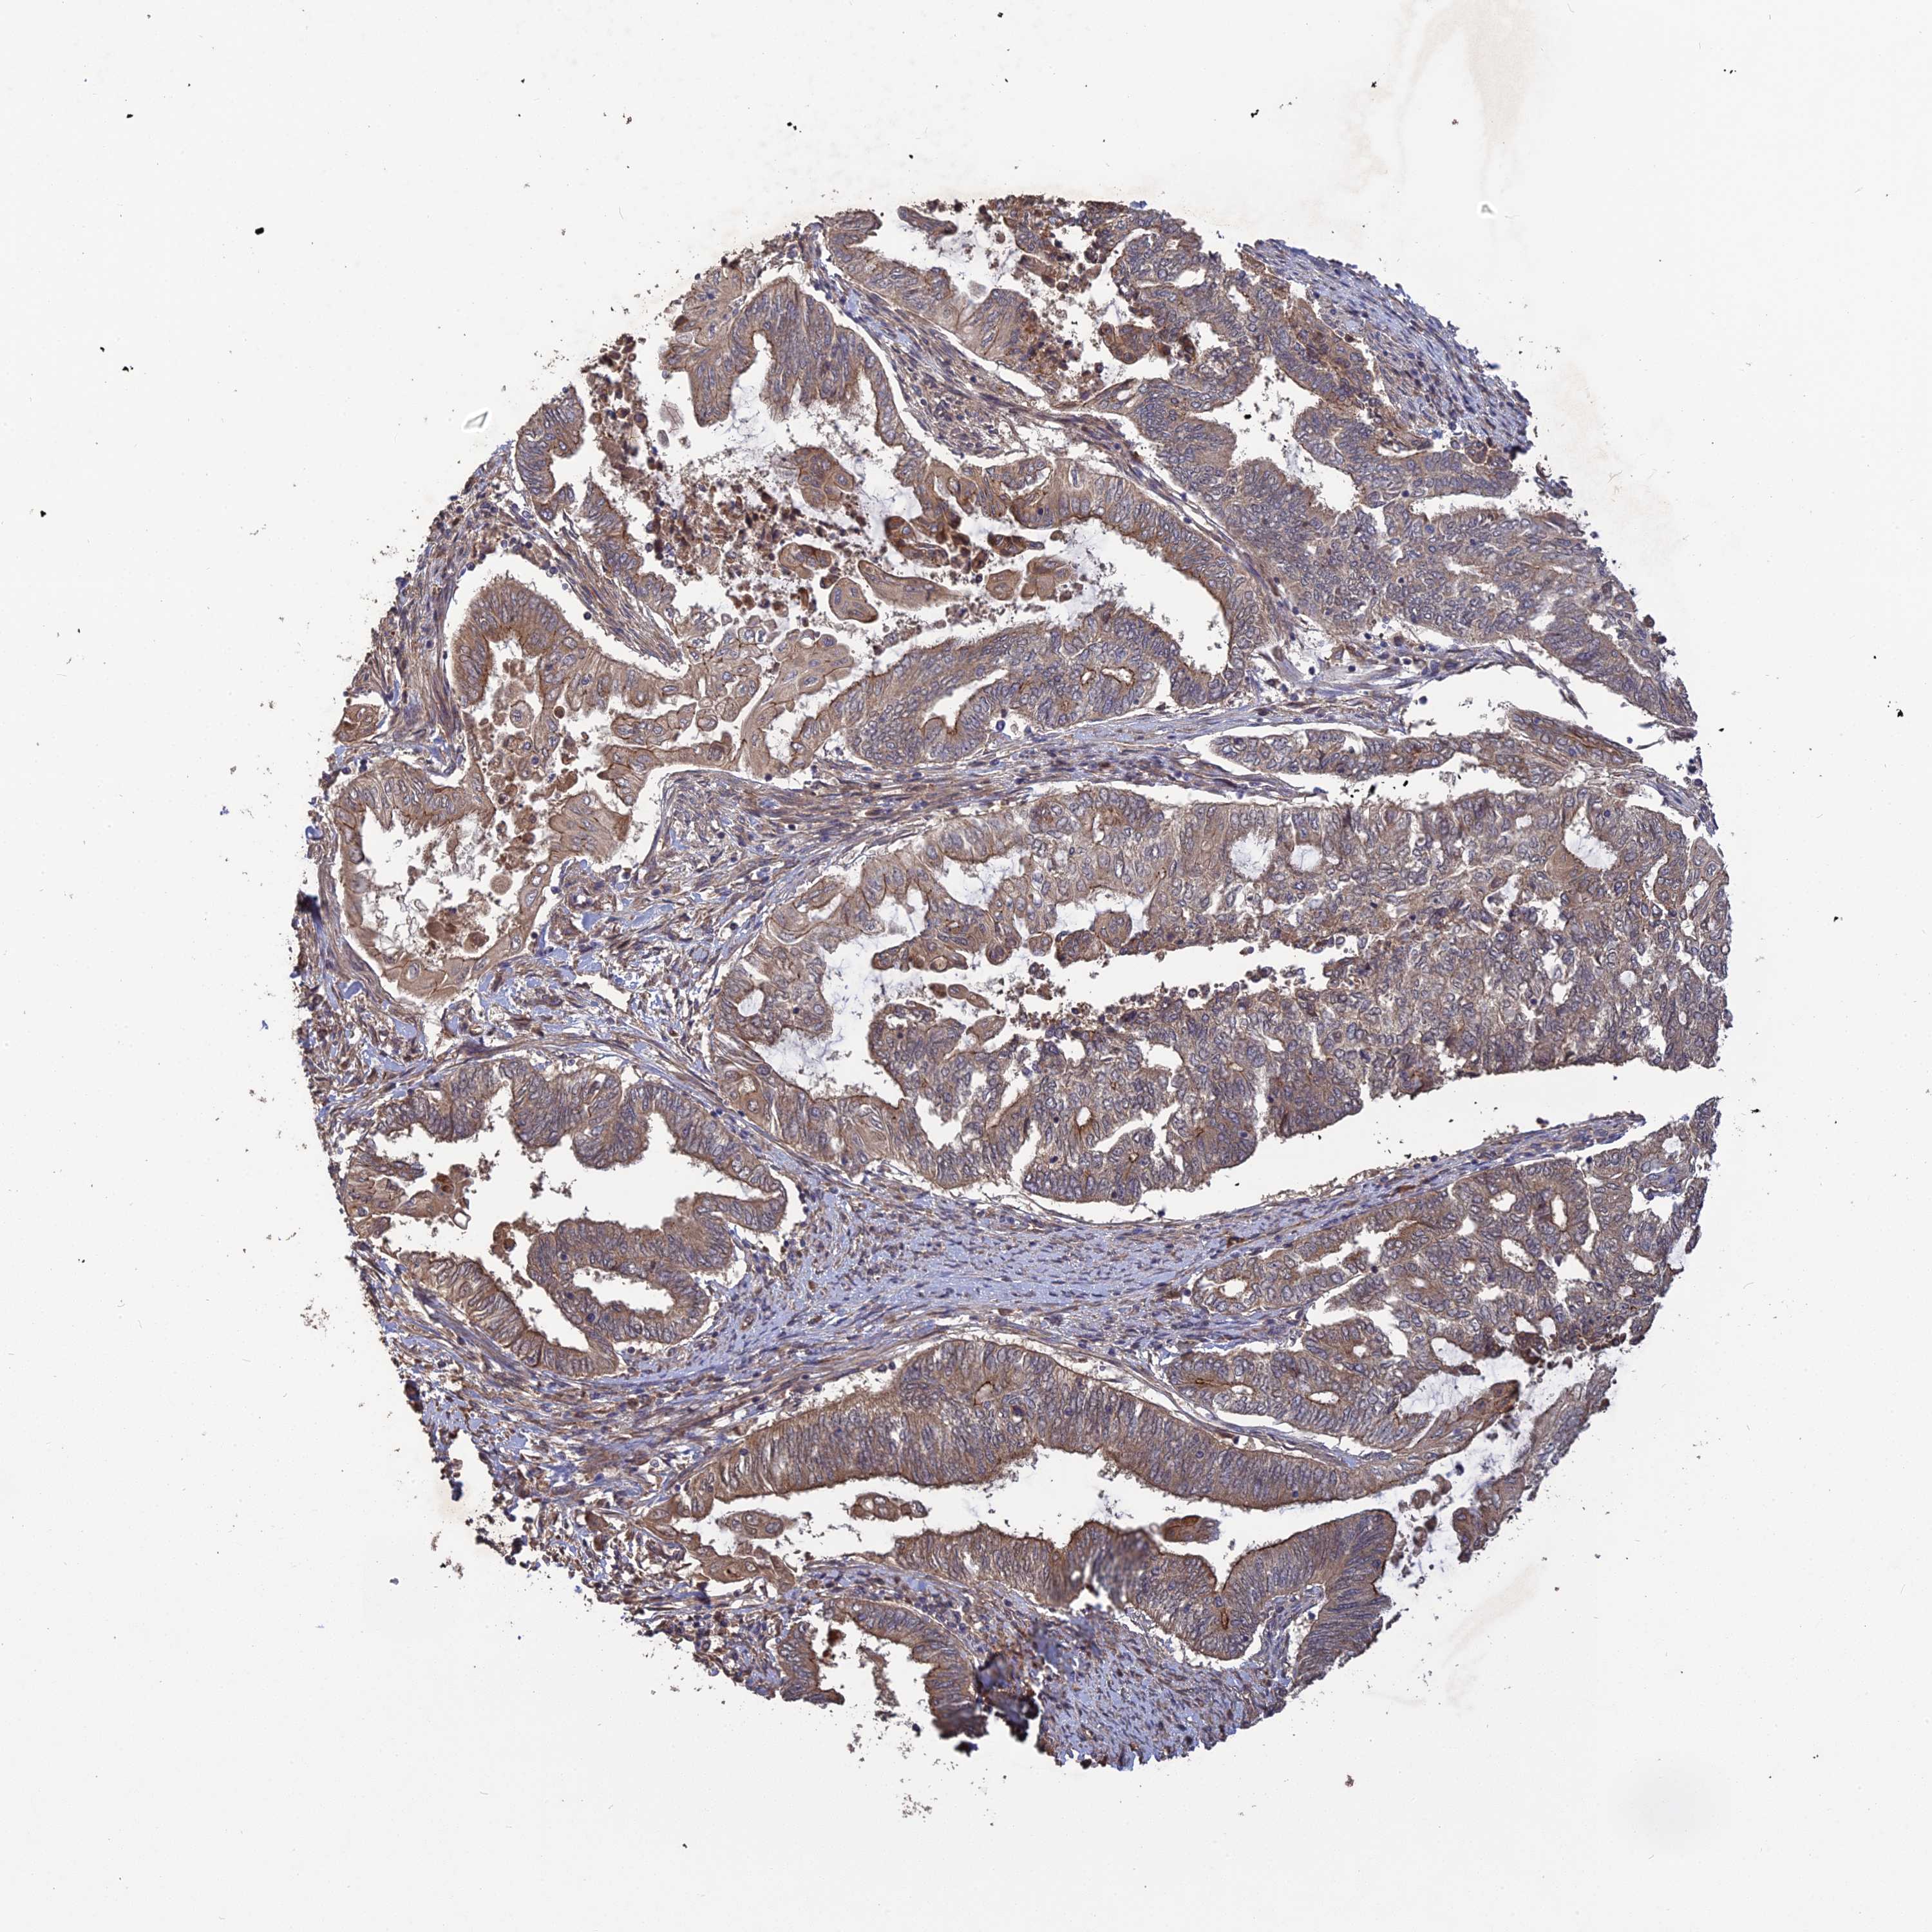

ENDOMETRIAL CANCER - Protein expressioni

A mouse-over function shows sample information and annotation data. Click on an image to view it in a full screen mode. Samples can be filtered based on level of antibody staining by selecting one or several of the following categories: high, medium, low and not detected. The assay and annotation is described here.

Note that samples used for immunohistochemistry by the Human Protein Atlas do not correspond to samples in the TCGA dataset.

Antibody stainingi

Antibody staining in the annotated cell types in the current human tissue is reported as not detected, low, medium, or high, based on conventional immunohistochemistry profiling in selected tissues. This score is based on the combination of the staining intensity and fraction of stained cells.

Each image is clickable and will lead to virtual microscopy that enables deeper exploration of all samples and also displays staining intensity scores, fraction scores and subcellular localization as well as patient and tissue information for each sample.

Antibody HPA042636

Antibody HPA042840

Staining

High

Medium

Low

Not detected

Intensity

Strong

Moderate

Weak

Negative

Quantity

>75%

75%-25%

<25%

None

Location

Nuclear

Cytoplasmic/membranous

Cytoplasmic/membranous,nuclear

Adenocarcinoma, NOS